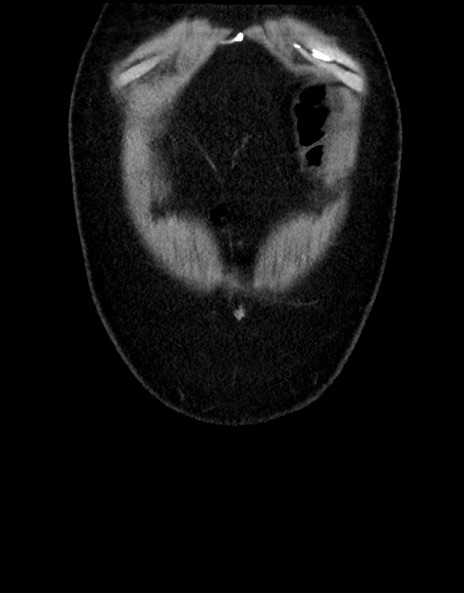

横断像